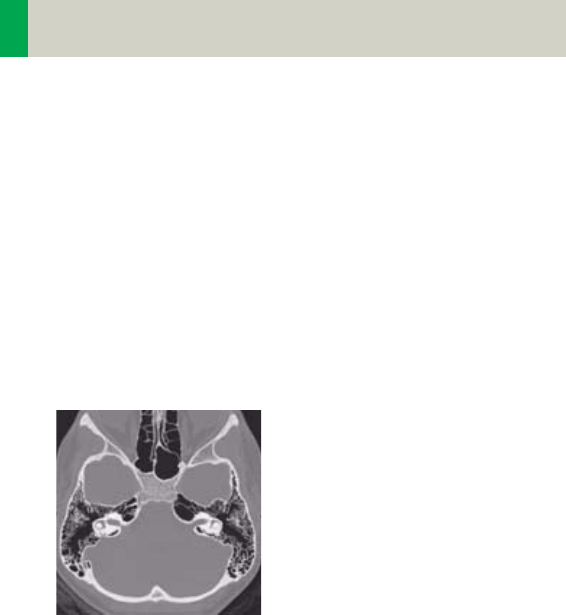

Head image without

correction.

Head image with

corrections.

Automatic Bone Correction

The head protocols provide significant improvements

regarding image quality for heads. An automatic bone

correction algorithm has been included in the standard

image reconstruction. Using a new iterative technique,

typical artifacts arising from the beam-hardening

effect, for example, Hounsfield bar, are minimized

without additional post-processing. This advanced

algorithm produces excellent images of the posterior

fossa, but also improves head image quality in general.

Bone correction is activated automatically for body

region “Head”. The reconstruction algorithm for “Head”

also employs special adaptive convolution kernels

which help to improve the sharpness-to-noise ratio.

More precisely, anatomic contours are clearly dis-

played while noise is suppressed at the same time

without causing a blurring of edges.